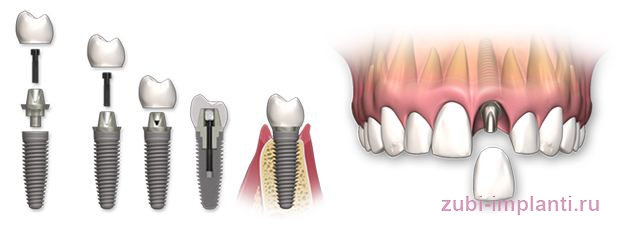

Современные коронки на зубные импланты: виды и фото-примеры